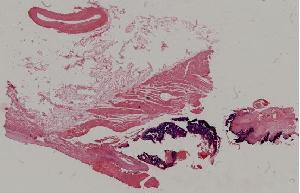

9. Healing of skin by first intention